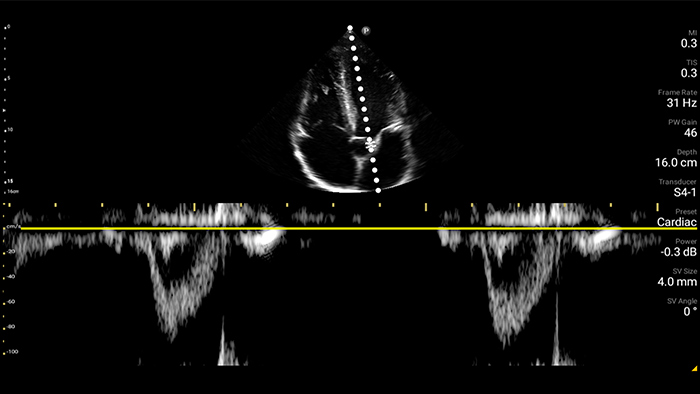

• Rango extendido de frecuencias de operación de 4 a 1 MHz • 2D, Doppler a color, Modalidad M, XRES avanzado e imágenes armónicas multivariables • Imagenología de alta resolución para aplicaciones abdominales y cardíacas: optimizaciones de preajustes de imágenes cardíacas, gineco-obstétricas, pulmonares, abdominales y FAST.

Desde revelar los detalles sutiles de una imagen hasta descubrir la definición del tejido enriquecido desde múltiples ángulos, Lumify puede ayudarlo a tomar decisiones en tiempo real con más confianza desde la evaluación hasta la recuperación.

Ultrasonido cardíaco en el punto de atención prehospitalario: embolia pulmonar